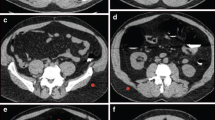

No significant difference was observed in the subjective scores between the ULDCTC and SDCTC, no matter in 2D or 3D images (all P>0.05). A good consistency of subjective image quality existed among the two reviewers (Kappa value 0.805~0.923, P<0.001). In both groups, no images were found to be non-diagnostic (Fig. 3). Representative examples are presented in Figs. 4 and 5.

A 70-year-old female with a 3.5-cm tubular adenocarcinoma in the distal rectum (BMI 22.89 kg/m2). The tumor is clearly depicted (red arrow) on the (a) 2D MPR reconstructed by 30% post-set ASIR-V, (b) 3D CTVC, and (c) 3D Raysum image, with an ED of 2.41 mSv. In the supine position, the tumor is well visualized (red arrow) on the (d) 2D MPR reconstructed by 80% post-set ASIR-V, (e) 3D CTVC, and (f) 3D Raysum images, with an ED of 0.70 mSv. After reducing the radiation dose by 70.95%, the image qualities of the supine images were still comparable to those of prone images